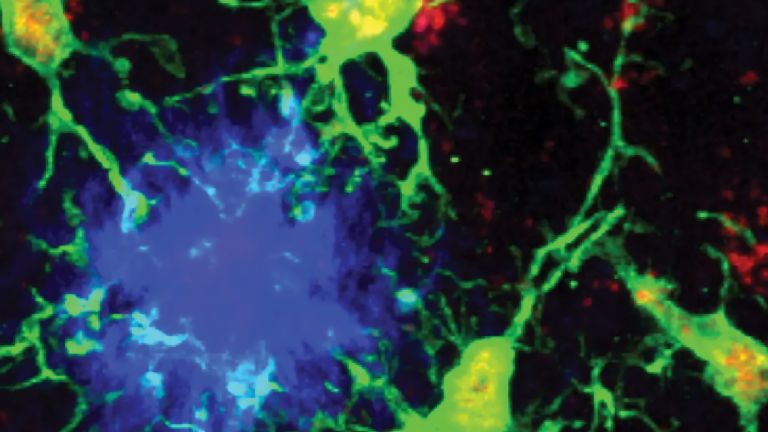

Mikroglia (grün) reagieren auf aggregierte Beta-Amyloid-Plaques (blau) im Kortex einer Maus.

In Alzheimer’s disease—the leading cause of dementia—microglia, the brain’s immune defenders, can act as both protectors and aggressors, shaping how the disease progresses. Researchers at the Max Planck Institute for Biology of Ageing in Cologne and the Icahn School of Medicine at Mount Sinai in New York, in close collaboration with The Rockefeller University, The City University of New York and multiple international partners, have identified a distinct population of neuroprotective  microglia, that may point to a new therapeutic approach for Alzheimer’s disease. In a study published in Nature, the team reports that microglia with reduced expression of the transcription factor PU.1 and co-expression of the lymphoid-like receptor CD28 act to limit neuroinflammation and to slow amyloid-plaque build-up and neurotoxic Tau protein spreading in the brain, the major hallmarks of Alzheimer’s pathology.

Using Alzheimer’s mouse models, human cells, and human brain tissue, the researchers demonstrated that lowering PU.1 promotes the expression of lymphoid immunoregulatory receptor proteins on microglia. Despite being present in small numbers, these neuroprotective microglia exert a brain-wide suppressive impact on inflammation and protect cognitive function and survival in mice. Deleting CD28 from this small subset of microglia amplified inflammation and accelerated plaque growth, highlighting CD28’s key role in protective microglial activity.